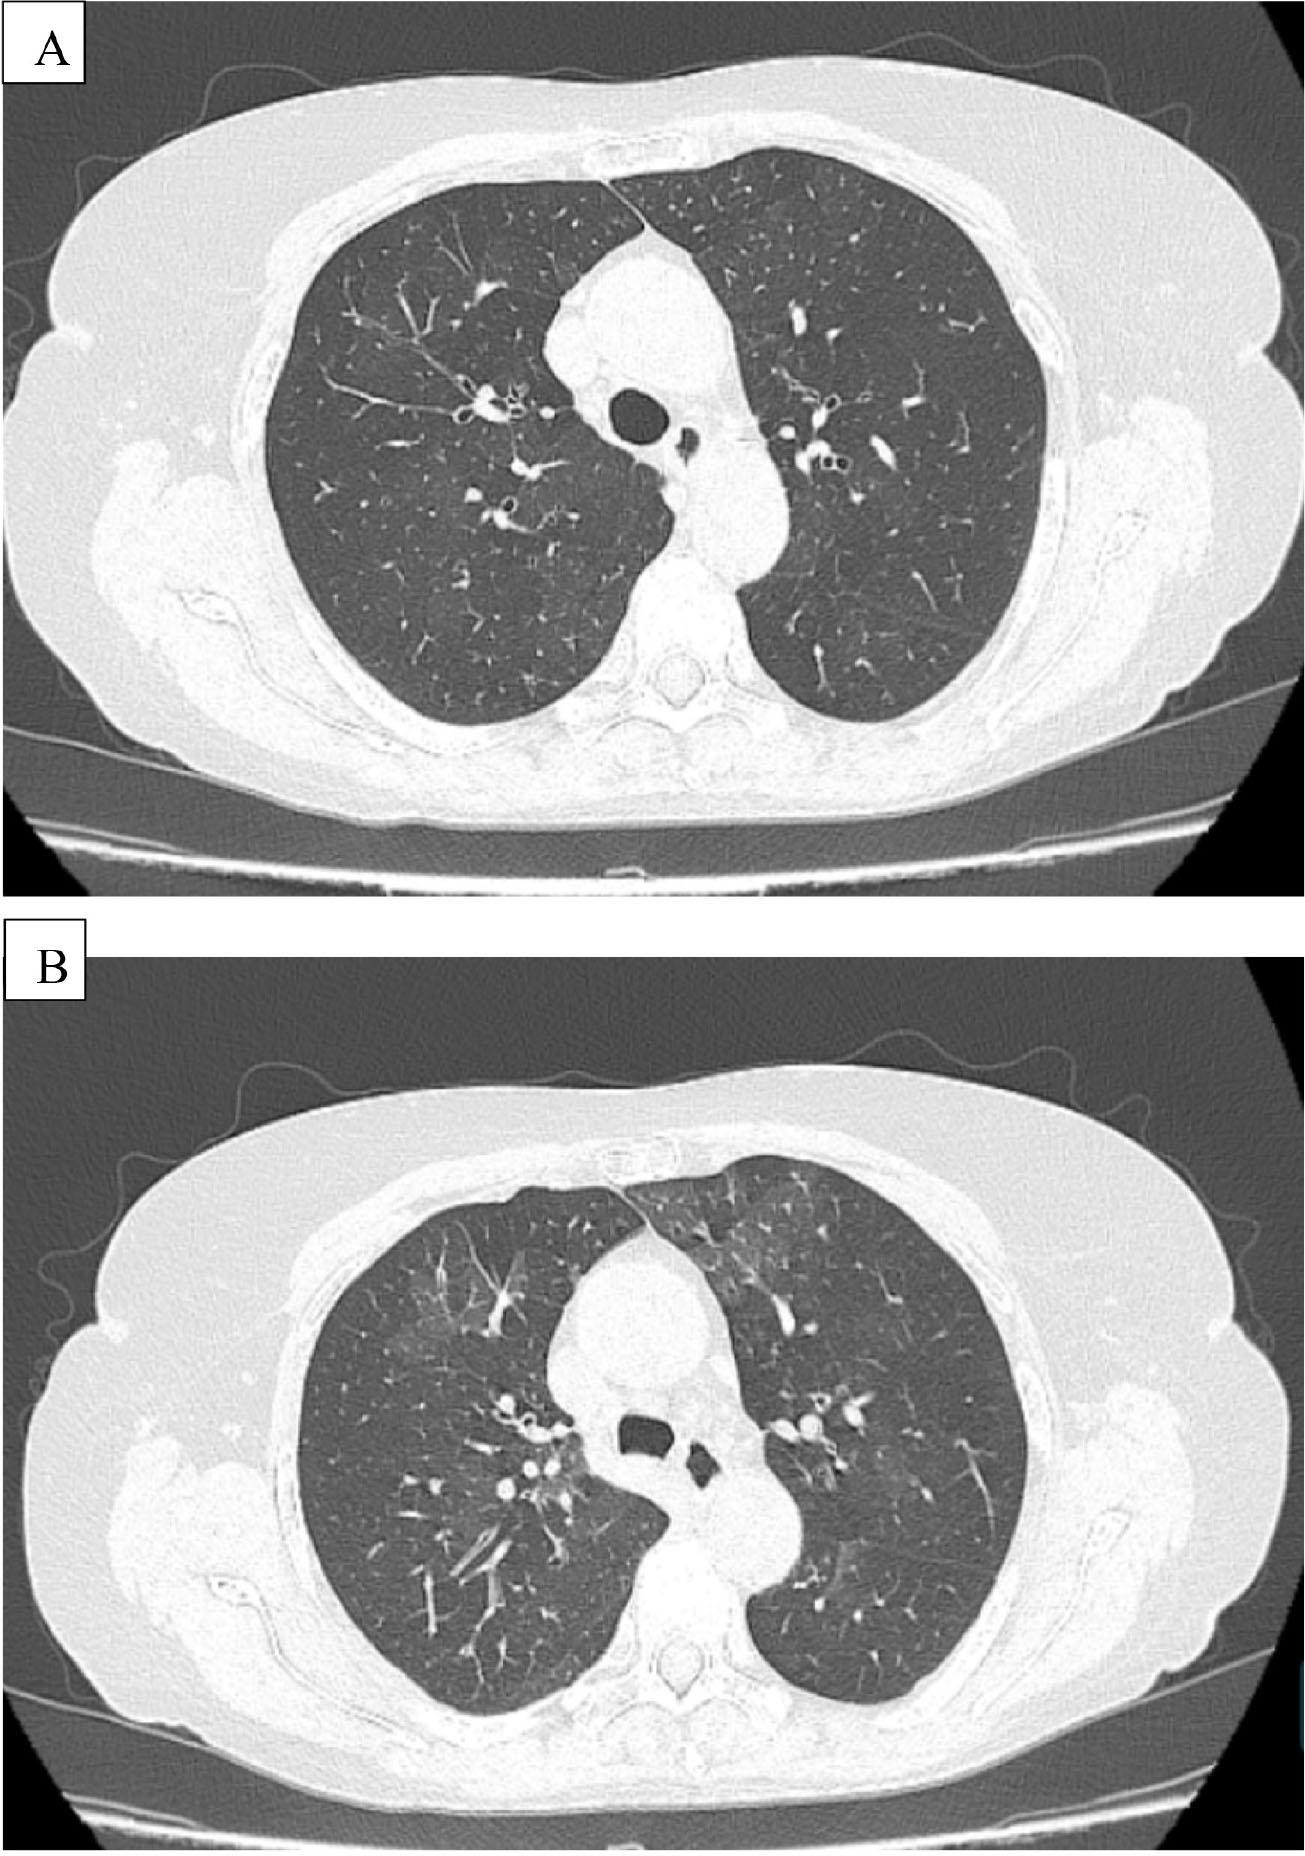

Figure 1.

| HR–CT | Mosaic attenuation | Mosaic attenuation | Increased lucency, predominantly in the basal regions |